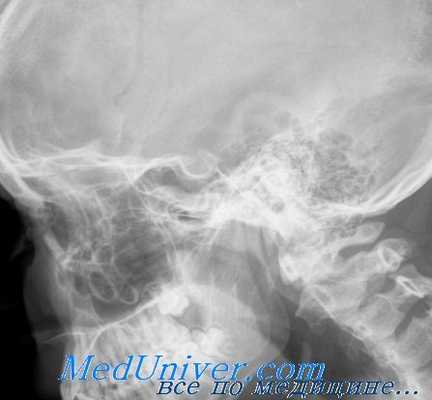

Ввиду того что при сифилитическом заболевании костей глазницы основным элементом является оссифицирующий процесс, рентгенологически это будет проявляться в виде диффузного или ограниченного затемнения. Однако для сифилитического процесса рентгеновская картина не является патогномоничной, особенно при диффузном периостите. Подобные же изменения могут наблюдаться и при других процессах, как, например, при травмах, опухолях и т. д., которые также способны вызвать реактивный гиперостоз стенки глазницы.

Следовательно, этиологический диагноз должен быть поставлен с „исключительной осторожностью и только на основе анамнеза, клинических данных и результатов анализа крови. Следует помнить, что периостит не всегда может быть выявлен рентгенологически, особенно в свежих случаях. Необходимо обратить внимание па состояние придаточных полостей носа, которые, как уже было сказано, играют немаловажную роль в воспалении костных стенок глазницы.

При ограниченном поражении костной стенки глазницы сифилитического характера отмечаются очаговые просветления с гиперостозом вокруг очага.

При локализации процесса вблизи зрительного отверстия контуры последнего кажутся стушеванными и могут быть более уплотненными по сравнению с другой, злоровой, стороной.

Верхняя глазничная щель при сифилитическом воспалении этой области становится более узкой, а края щели стушеванными. Нужно отметить, что в некоторых случаях и в норме наблюдается асимметрия в ширине верхней глазничной щели обеих глазниц.